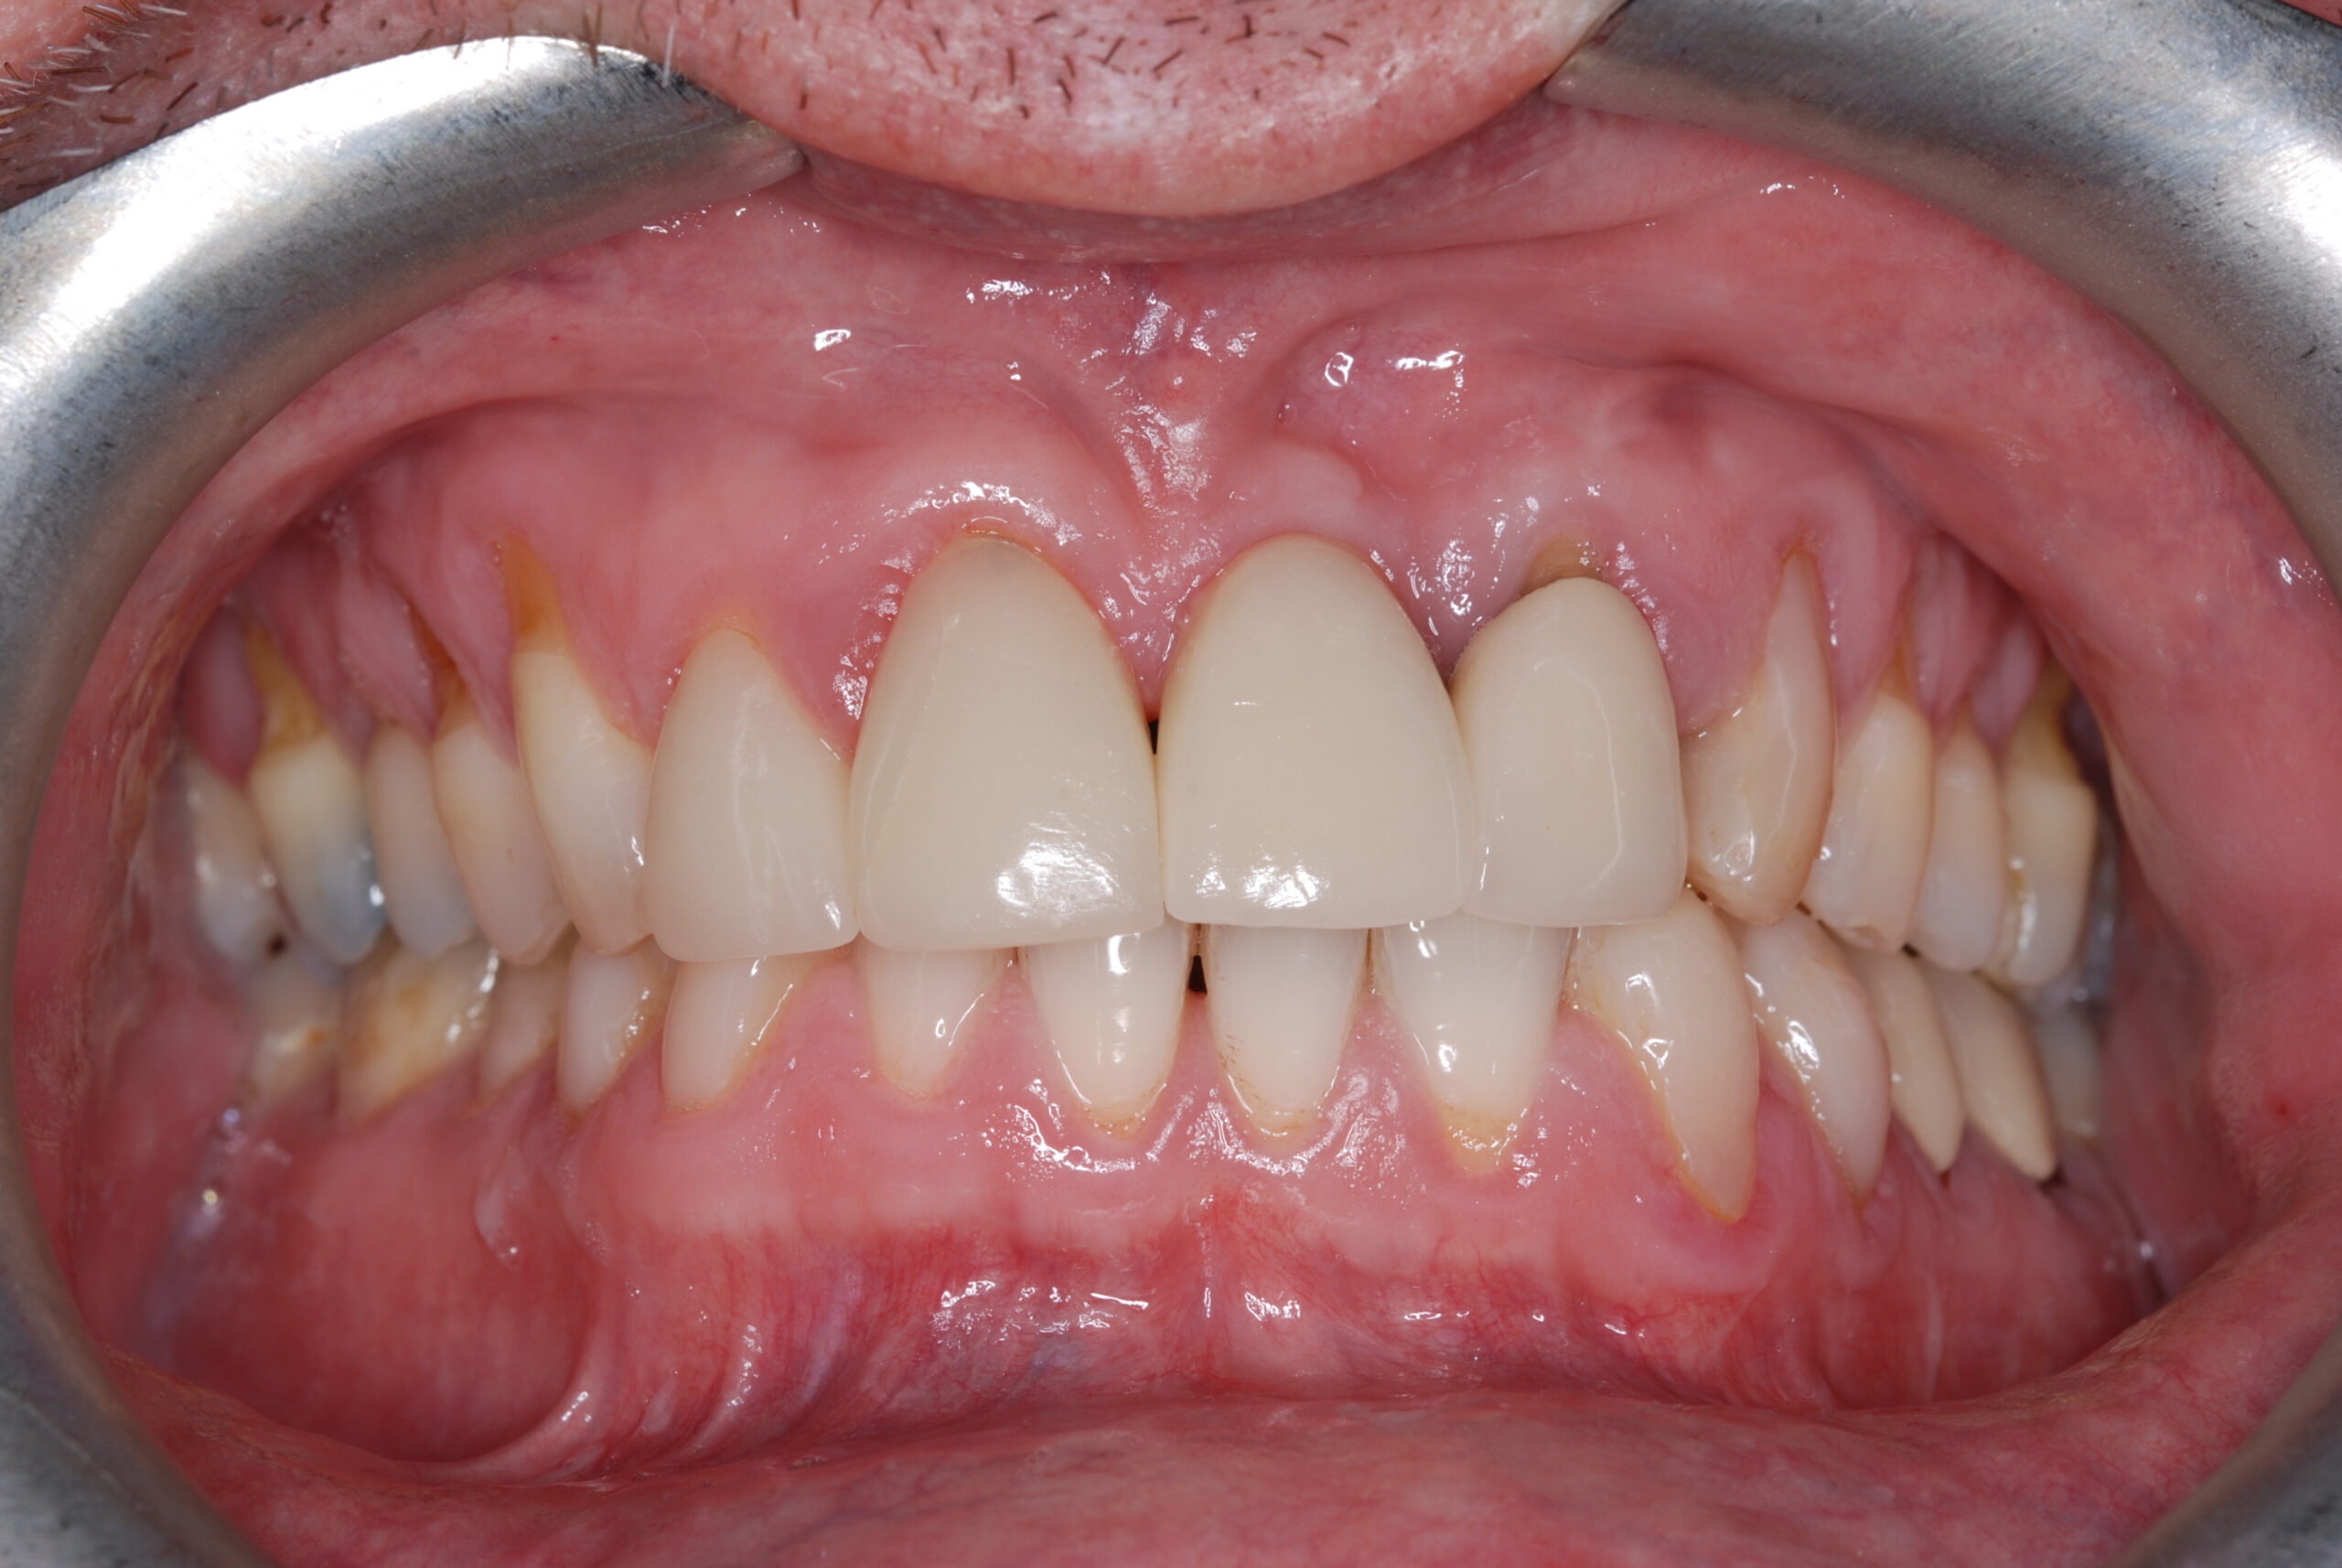

Treatment with dental implants has provided patients with a proven option to replace missing teeth for many years. Developments in the materials and techniques used have now made them the gold-standard for tooth replacement, and they avoid many risks and disadvantages of alternatives such as bridges and dentures.

Losing a tooth often leads to there being a visible gap between the other teeth which can be unsightly and upsetting. Conventional dentistry such as dental bridges involves drilling into adjacent teeth that may be perfectly healthy. Implants avoid the need to drill into any other teeth, and therefore avoid possible complications such as infection, fracture, and ultimately the loss of these teeth.

Dental implants can be used to replace a single missing tooth, multiple teeth, or all teeth.